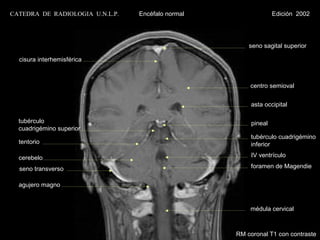

CATEDRA DE RADIOLOGIA U.N.L.P.   Encéfalo normal                 Edición 2002

seno sagital superior

cisura interhemisférica

centro semioval

asta occipital

tubérculo                                             pineal

cuadrigémino superior

tubérculo cuadrigémino

tentorio                                              inferior

cerebelo                                              IV ventrículo

seno transverso

agujero magno

médula cervical

RM coronal T1 con contraste